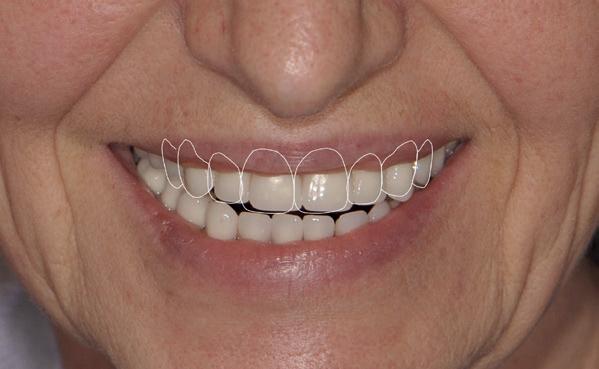

In de prothetische fase (zie foto’s) is in de bovenkaak gebruikgemaakt van verschroefde zirconia bruggen, die enkel buccaal zijn opgebakken. Deze bruggen zijn verlijmd op individuele, geanguleerde titanium abutments. In de onderkaak is een verschroefde kunststofbrug op een titaniumbasis (wrap-around) gemaakt. Voor deze combinatie is gekozen vanwege een minder hinderlijk tikkend geluid bij functie en kleinere kans op breuk van de keramiek. Een nadeel is verhoogde slijtage van de kunststof elementen, maar deze zijn in de jaren later eenvoudig te vervangen op de bestaande brug. Ondanks alle digitale mogelijkheden is de afdruk en registratiefase analoog uitgevoerd, omdat in ervaring van de behandelaren dit bij deze totale rehabilitaties op implantaten nog altijd de grootste precisie oplevert. Er is afgedrukt met impregum in individuele lepels en de pasvorm is gecontroleerd met rigide duralay bars. De relatie wordt vastgelegd zoals bij een volledige prothese met waswallen en pijlpuntregistratie. De opstelling in was wordt gepast en laatste correcties worden gemaakt in samenspraak met de patiënt, de restauratieve tandarts en de tandtechnicus. Na het vastzetten van de suprastructuren worden de schroefgaten afgesloten met composiet.

in de zes maanden bij de mondhygiënist voor peri-implant reiniging, pocketmetingen, mondhygiëne instructies en controles. De AirFlow wordt daarbij standaard gebruikt. Verder wordt de patiënt na één, drie en zes jaar gezien voor controle van de suprastructuren door de restauratieve tandarts. Uit de röntgenfoto’s kan afgeleid worden dat het botniveau gelijk blijft over tijd. Klinisch ziet de situatie er infectievrij uit; de patiënt onderhoudt het zelf netjes met ragertjes, een elektrische tandenborstel als ook de Waterpik.

uitgevoerd met restauratief tandarts Paul de Kok, KVPA). 12. Eindresultaat.